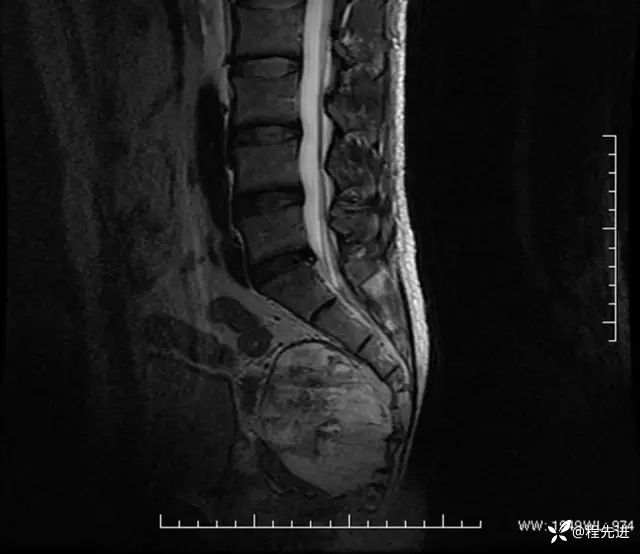

T2矢状位: